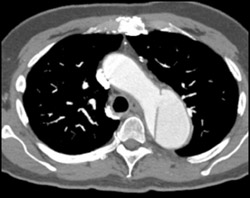

Aortic Dissection